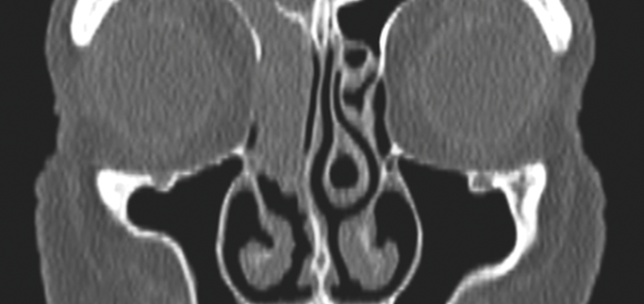

Superior semicircular canal dehiscence: transmastoid obliteration